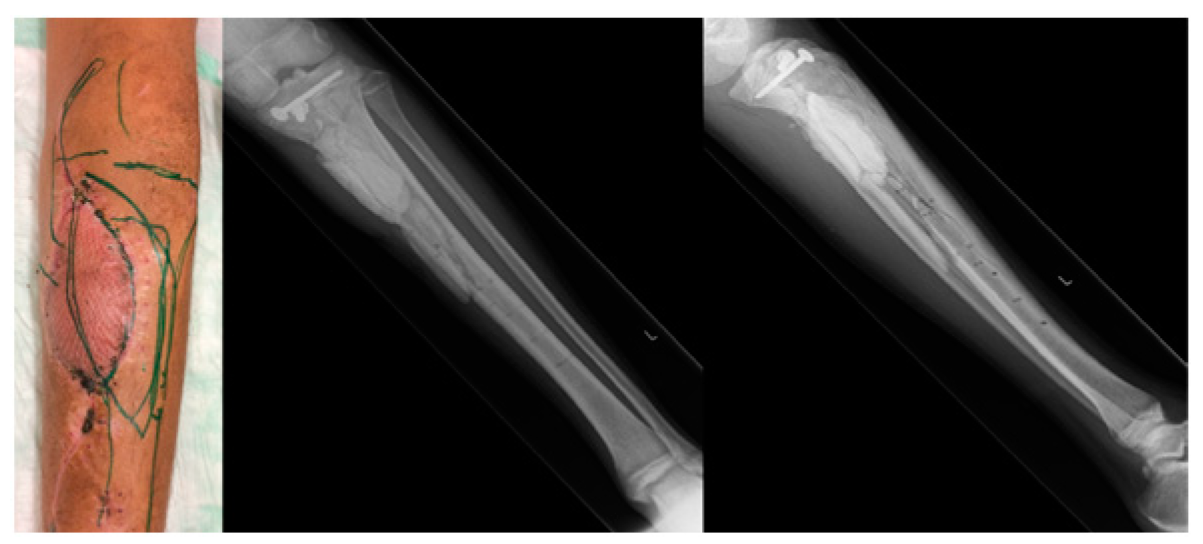

2. Case Description